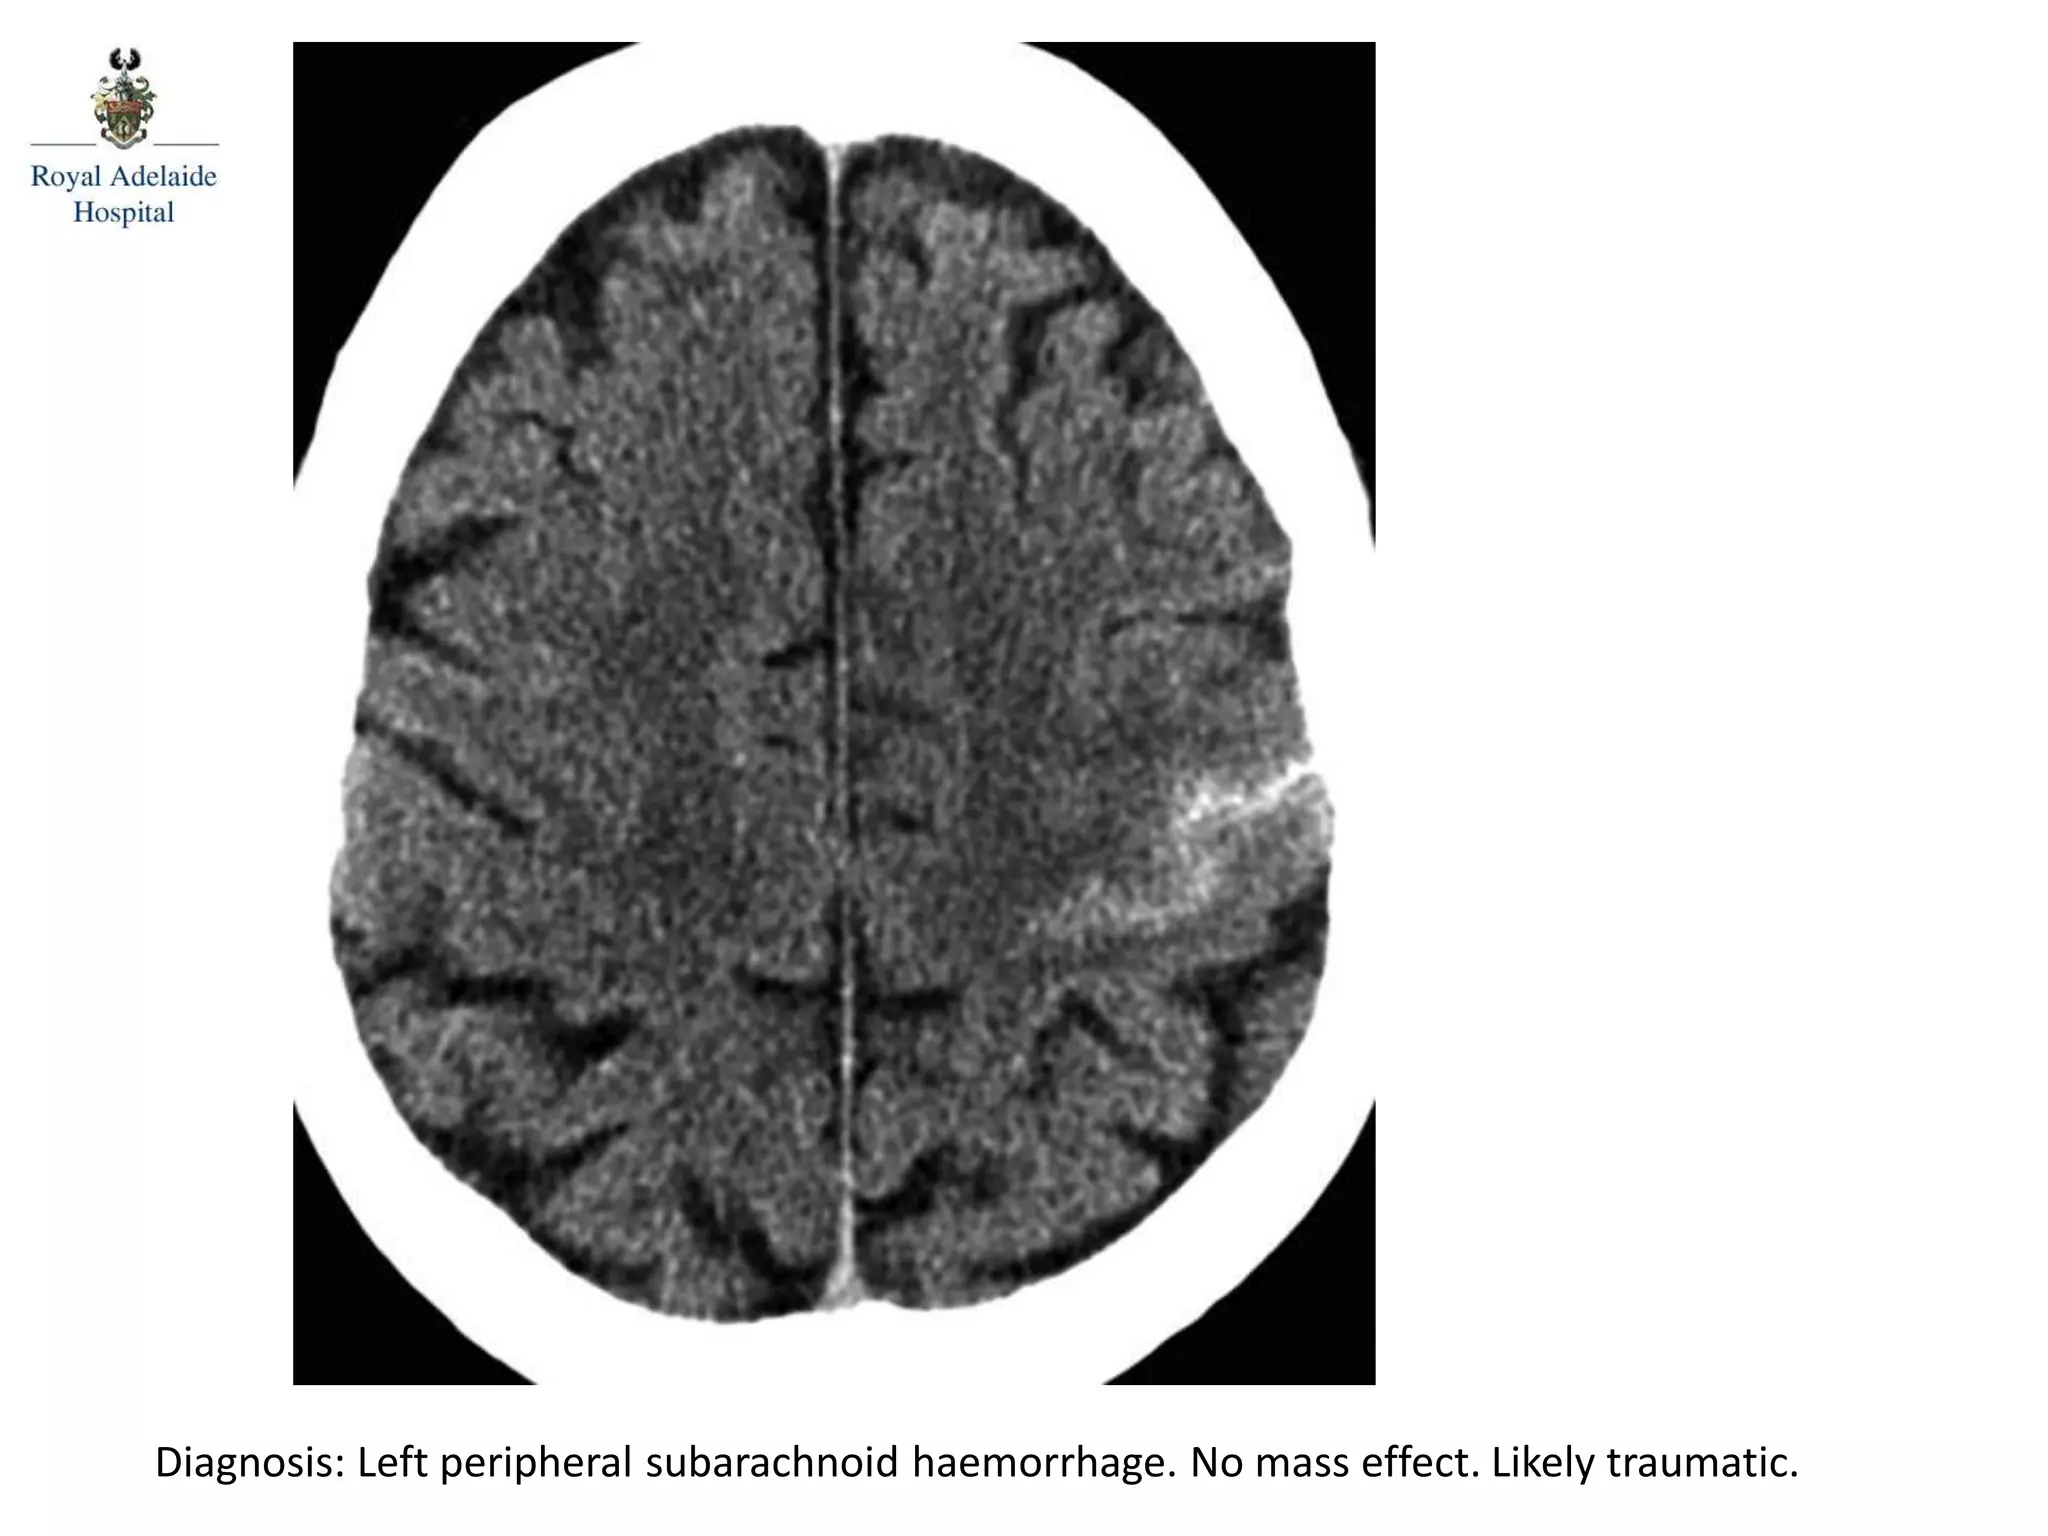

The document outlines multiple diagnoses from head CT cases, including small left basal ganglia bleed likely due to hypertension, various types of subdural and subarachnoid hemorrhages, and evidence of hydrocephalus. It details traumatic origins of some hemorrhages and notes obstructing masses and atrophic changes. Overall, there are significant findings indicating complications related to cerebral hemorrhages and ventricular enlargement.